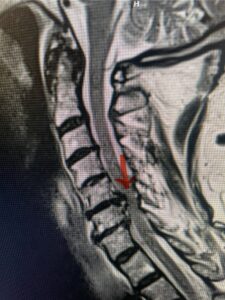

The case illustrates a more subtle finding of cervical myelopathy in a young 52 year-old male who presents with 5 months of left upper extremity weakness and burning. He also had developed over the last two months pain in his right upper extremity. He also had difficulty with fine motor skills. He had a positive Hoffman reflex and mild 4-4+ long tract weakness of his left arm and leg. Cervical MRI revealed an explanation for the patient’s symptoms (Fig. 7) as it revealed a disc osteophyte complex causing some cord flattening, slightly more to the left. We performed a C5-6 anterior cervical discectomy and interbody fusion with cage and plate (Fig. 8) He had a significant improvement in his weakness, numbness, and pain. What is interesting is that this was a relatively young patient without severe cord compression but was significantly affected by a mild amount of cord compression. This may speak to how a younger spinal cord may react much more adversely perhaps secondary to a less compliant spinal cord.

Fig. 7a Sagittal and axial T2-weighted cervical MRI’s demonstrating spinal cord compression slightly to the left secondary to disc/osteophyte complex (red arrow)

Fig. 7b

Fig 8: lateral intraoperative cervical x-ray demonstrating placement of interbody cage and plate at C5 6 (red arrow)